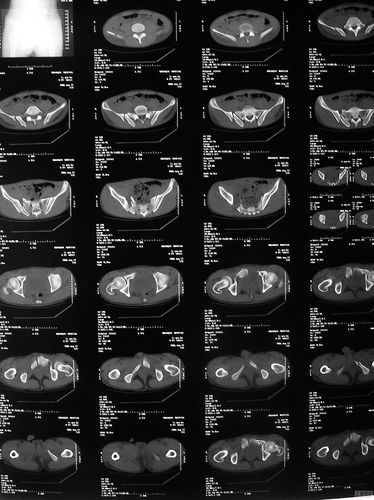

骨盆ct平扫图片解剖图

骨盆ct平扫图片解剖图,骨盆ct断层解剖图

术前ct平扫

骨盆,股骨头平扫

骨盆ct断层解剖图

正常骨盆ct平扫图片

骨盆ct断层解剖图骨窗

骨盆CT解剖